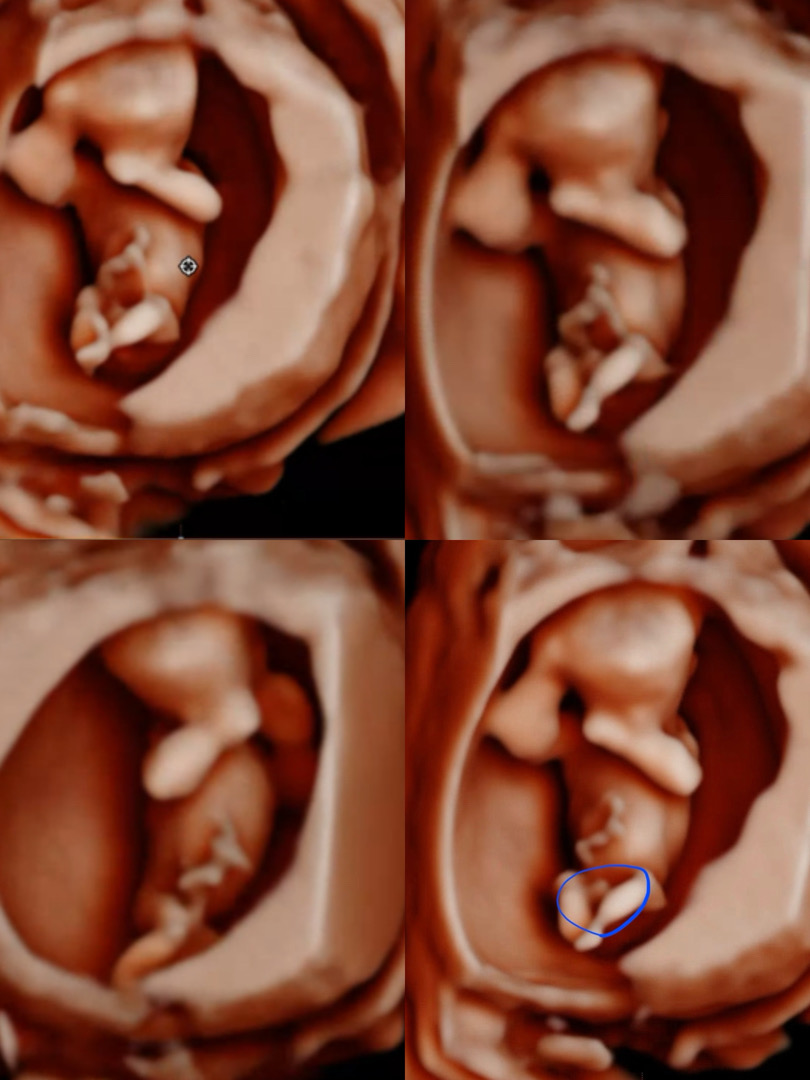

12주차 3일 촬영 / 🌶️일까요? 탯줄일까요?

많은 의견 부탁드립니당🫶🏻